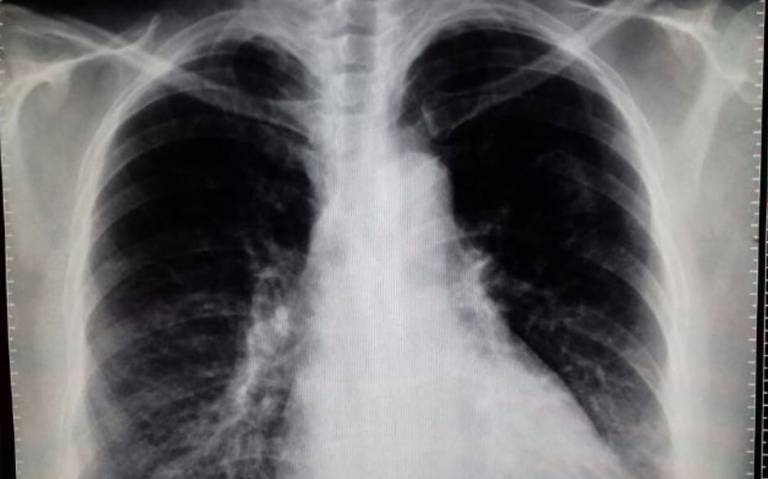

Corticosteroides sistémicos, mortalidad e infecciones en la neumonía y el síndrome de dificultad respiratoria aguda

En la neumonía grave y en el sindrome de distress respiratorio del adulto (SDRA), los corticosteroides adyuvantes probablemente reducen la mortalidad a corto plazo. En la neumonía grave, pueden reducir el shock secundario. En ambas afecciones, los corticosteroides pueden tener poco o ningún efecto sobre las infecciones nosocomiales. Annals of Internal Medicine, diciembre de 2025.